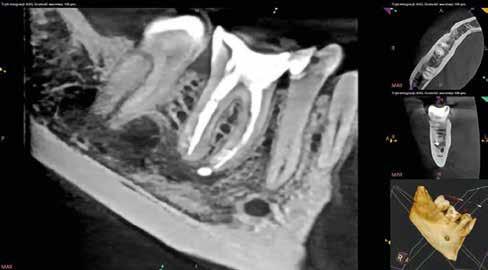

A következő pácienst egy betört eszköz eltávolítása és a gyökérkezelés befejezése céljából irányították dr. Witkowski rendelőjébe (9. ábra). Az eltávolítás során várhatóan jelentkező nehézségek és a perforáció megnövekedett esélye miatt a páciensnek a betört eszköz mellett történő elhaladást javasoltuk, amelyet ő el is fogadott. A mesialis és a distalis csatornákat R25 RECIPROC blue gépi gyökérkezelő tűkkel a teljes munkahosszon feltágítottuk (VDW) (10. a–f ábra). Ezután a gyökércsatorna-rendszert alaposan átöblítettük és az átöblítőszereket szonikusan aktiváltuk (11. a–d ábra). A gyökércsatornákat kiszárítottuk, majd a dugattyú technika alkalmazása mellett letömtük (12. a–c ábra). Ezzel az eljárással képesek vagyunk a mechanikai megmunkálás során nem érintett gyökércsatorna-szakaszok feltöltésére, illetve még olyan esetekben is nagyon egyszerűen alkalmazható, mint amikor valamilyen mechanikai akadály (pl.: egy betört eszköz) található a gyökércsatorna belsejében (13. ábra).

A gyökerek mélyén történő gyökércsatorna-elágazódás midig jelentős kihívást jelent a kezelést végző orvosok számára. Ez különösen igaz azokban a helyzetekben, amikor korlátozott a hozzáférés, vagy rendkívül szűk területen kell dolgozni. A páciens egy egyszerű fogászati beavatkozás (a szuvasság eltávolítása és tömés készítése) miatt kereste fel a rendelőnket (14. ábra). A kezelések megkezdése előtt kiindulási röntgent készítettünk (15. ábra). A szuvas lézió feltárása és a szuvas foganyag eltávolítását követően szükség volt gingivectomia végzésére, mivel a meziális üregszél szubgingivális helyzetbe került (16. a–d. ábra). Az izolálás felhelyezését követően a vonatkozó szakmai protokolloknak megfelelően építettük fel a hiányzó meziális falat. Ezután a hozzáférési nyílást ultrahangos eszközök segítségével kissé kiszélesítettük (17. a–d ábra). A gyökércsatornát az oszlásig R25 RECIPROC blue gépi gyökértágítóval tágítottuk fel, majd az oszlás alatti csatornaszakaszokat 12.5/.04 R-PILOT (VDW)

tágítóval munkáltuk meg (18. a–b ábra). A végső átöblítés során nátrium-hipokloritot, citromsavas oldatot és desztillált vizet alkalmaztunk (19. a–b ábra).

A gyökértömés elkészítése során a dugattyú technikát alkalmaztuk, majd a fogat kompozittömés segítségével állítottuk

helyre (20. a–d ábra). A végleges koronai restaurátumelkészítés céljából a pácienst továbbirányítottuk. A kontroll

CBCT-felvételen jól látható, hogy a dugattyú technika eredményes volt és csúcsig érő falálló gyökértömést tudtunk készíteni (21. a–d ábra).